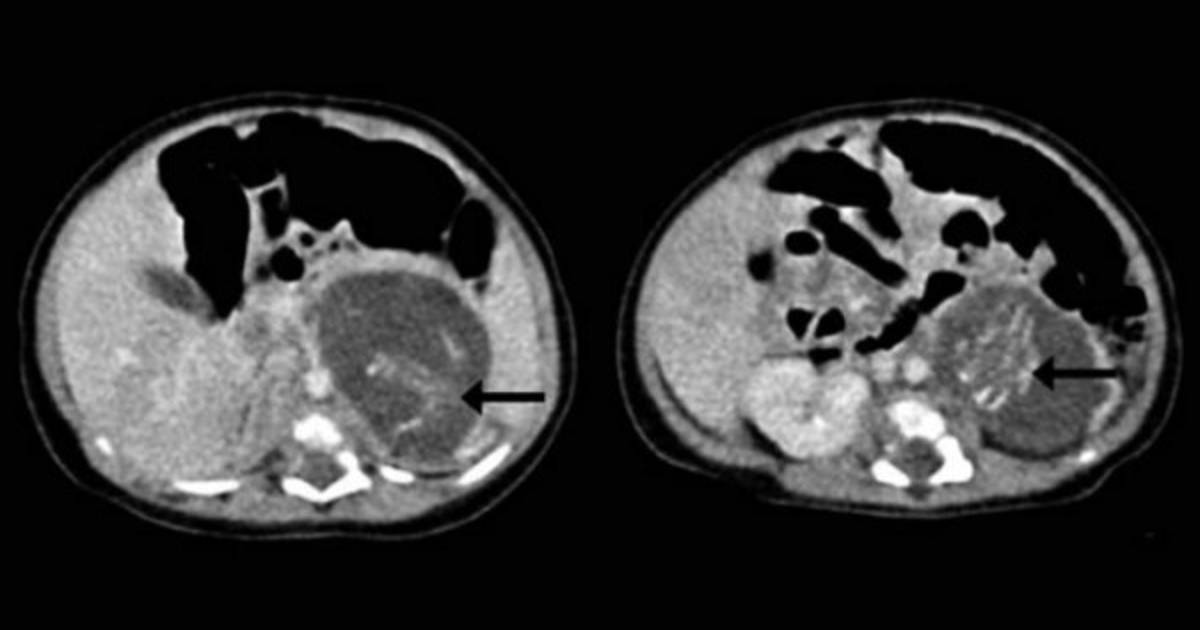

Un equipo de doctores describió el caso de una bebé recien nacida 'embarazada de gemelos' como un hecho médico extremadamente raro, tras encontrar lo que parece ser un par de fetos dentro del cuerpo de la bebé.

Los festos estaban unidos por cordones umbilicales en una clase de masa de placenta. Cada uno tenía cuatro miembros, piel, costillas, intestinos y tejido cerebral primitivo, de acuerdo con la publicación.

La razón de este extraño suceso, según afirman los especialistas, se debió a una fecundación errónea en el vientre de la madre, la cual habría producido que los fetos (sus dos hermanos) se gestaran en su interior. El caso, con todo, es conocido. Se llama 'fetus in fetu' y sólo se produce una vez en cada 500,000 nacimientos.

Las dos formas encontradas tenían diferentes pesos pero igual desarrollo de órganos, coincidente con un feto de 10 semanas de gestación. Tenían espinas dorsales y “genitales externos ambiguos”, aunque no contaban con cráneos.